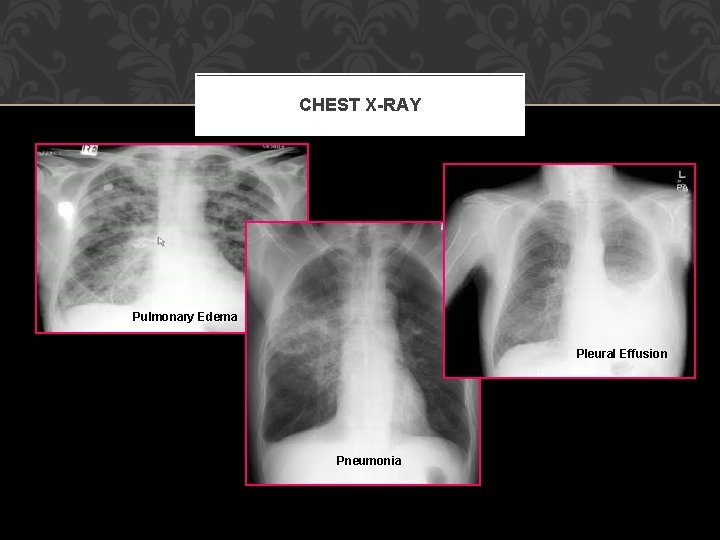

CHEST X-RAY Pulmonary Edema Pleural Effusion Pneumonia

PULMONARY COMPLICATIONS Atelectasis – peripheral alveolar collapse due to shallow tidal breaths, MC cause of fever within 48 h Aspiration pneumonitis – only requires 0. 3 ml per kilogram of body weight (20 to 25 ml in adults) Nosocomial pneumonia Pulmonary edema – CHF, ARDS Pulmonary embolus – 1/5 are fatal, greatest management = prevention